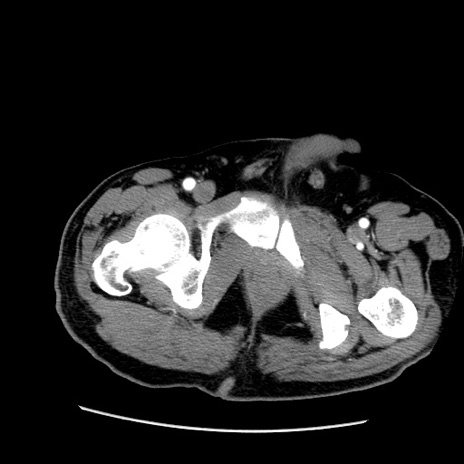

症例22(横断像)

【症例】50歳代男性

【主訴】腹痛

【現病歴】AVMからの被殻出血のため回復期リハ病棟入院中。 本日午後3時頃急に下腹部痛が出現した。

【既往歴】AVM、被殻出血、虫垂炎、高血圧

【身体所見】意識晴明、左半身不全麻痺、会話の理解は良好、36.5°C、腹部:膨隆、全体に板状硬、下腹部正中に圧痛点あり、反跳痛-、筋性防御不明、右下腹部にope scar

【データ】WBC 9400、CRP 0.06